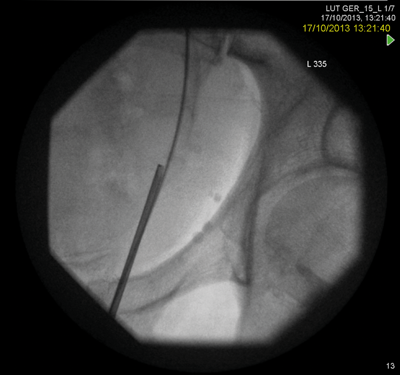

A rendezvous procedure was performed in the supine oblique position. The radiologist punctured the non-dilated kidney, feeding a wire antegradely to the bladder, allowing subsequent ureteroscopy and stone clearance.